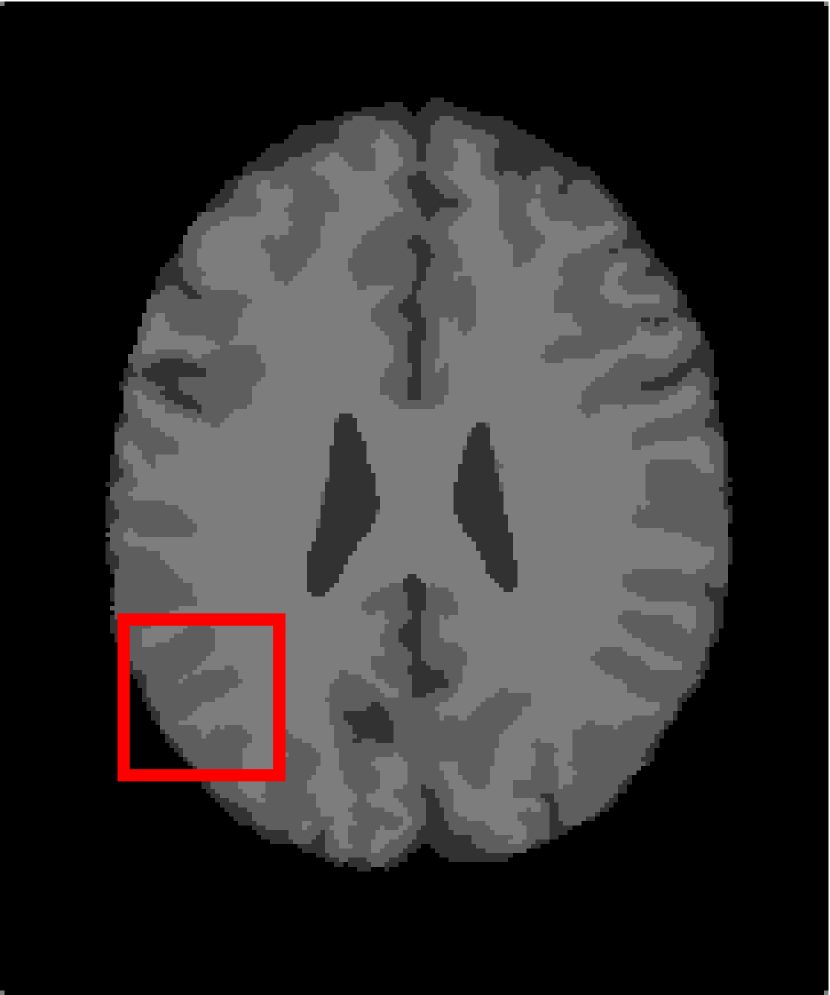

4.4.2 Results on Medical Images

Next, we representatively segment five medical images from BrianWeb. They are represented as five slices in the axial plane with a sequence of 70, 80, 90, 100 and 110, which are generated by T1 modality with slice thickness of 1mm resolution, 9% noise and 20% intensity non-uniformity. Here, we set c=4𝑐4c=4 for all cases. The comparison between WRFCM and its peers are shown in Fig. 9 and Table II. The best values are in bold.

Figure 9: Segmentation results on five medical images. The parameter: ϕ=5.35italic-ϕ5.35\phi=5.35. From top to bottom: noisy images, ground truth, and results of FCM_S1, FCM_S2, FLICM, KWFLICM, FRFCM, WFCM, DSFCM_N, and WRFCM.

TABLE II: Segmentation performance (%) on medical images in BrianWeb

Algorithm Fig. 9 column 1 Fig. 9 column 2 Fig. 9 column 3 Fig. 9 column 4 Fig. 9 column 5

SA SDS MCC SA SDS MCC SA SDS MCC SA SDS MCC SA SDS MCC

FCM_S1 75.756 97.852 96.225 75.026 98.109 96.656 79.792 98.452 97.334 81.887 98.614 97.680 81.869 94.254 90.947

FCM_S2 75.769 98.119 96.664 74.970 98.176 96.765 79.886 98.458 97.338 82.073 98.625 97.695 81.788 98.223 97.195

FLICM 74.998 98.070 96.568 74.185 98.122 96.660 79.099 98.515 97.432 81.447 98.627 97.691 81.668 98.273 97.260

KWFLICM 74.840 98.259 96.878 73.839 97.860 96.190 79.560 98.453 97.316 81.887 98.482 97.443 81.370 98.297 97.286

FRFCM 75.853 97.620 95.775 75.514 97.660 95.830 80.283 98.278 97.013 81.852 98.319 97.171 81.666 98.079 96.945

WFCM 75.507 97.124 94.957 74.471 97.213 95.045 79.316 97.845 96.283 81.358 97.546 95.211 81.452 95.247 92.501

DSFCM_N 76.400 92.325 86.262 75.288 91.574 85.095 79.861 97.678 95.996 81.831 93.304 88.829 81.750 94.302 91.024

WRFCM 82.317 98.966 98.147 82.141 98.298 96.970 83.914 98.963 98.202 83.533 99.170 98.603 84.615 98.429 97.511

By a view of the marked red square in Fig. 9, we find that FCM_S1, FCM_S2, FLICM, KWFLICM and DSFCM_N are vulnerable to noise and intensity non-uniformity. They give rise to the change of topological shapes to some extent. Unlike them, FRFCM and WFCM achieve sufficient noise removal. However, they produce overly smooth contours. Compared with its seven peers, WRFCM can not only suppress noise adequately but also acquire accurate contours. Moreover, it yields the visual result closer to ground truth than its peers. As Table II shows, WRFCM obtains optimal SA, SDS and MCC results for all five medical images. As a conclusion, it outperforms its peers visually and quantitatively.